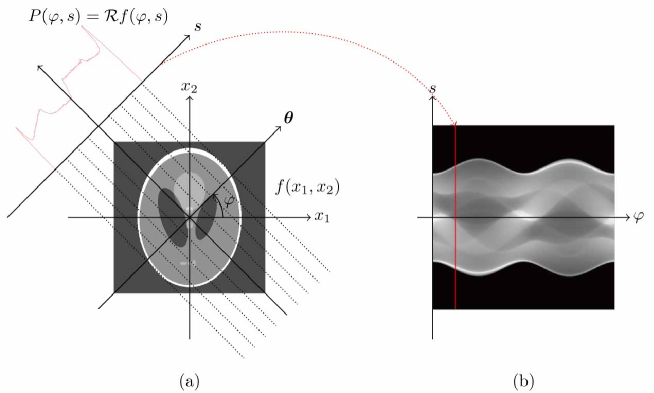

This paper aims, through rigorous mathematical analysis, to characterize the structure of metal streaking artifacts. The artifacts arise because of the mismatch between the CT image reconstruction algorithm (filtered back projection (FBP) algorithm Bracewell1967 ) and the nonlinear variation in the X-ray data that occurs in the presence of a metallic object. In CT, X-ray projection data are collected for a slice after passing X-ray beams in different directions through an object, where indicates the position of the projected line and is the angle of the projection as shown in Fig. 1. The FBP algorithm is based on the assumption that the X-ray projection data is in the range of the Radon transform Radon2005 , with its domain being , the space of distributions whose supports are compact; accepting this assumption, there exists in such that

where is the adjoint of Radon transform given by , and is the Riesz potential given by . FBP works well for CT imaging because for most human tissues, the X-ray data approximately satisfy the linear assumption of (1).